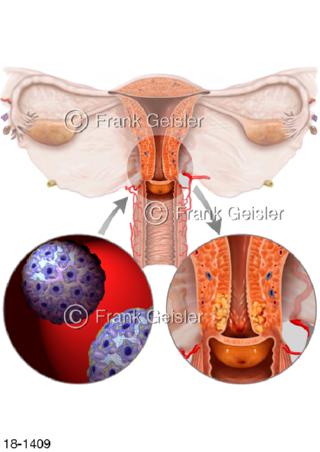

18-1409 Zervixkarzinom Gebärmutterhalskrebs